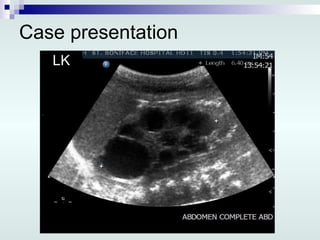

Case presentation 1 st  day of life: Abdominal and renal US: Lt multicystic dysplastic kidney, 7.3 x 4.1 x 4.8 cm Rt kidney smallish, 3.2 x 2.1 x 1.8 cm Urinary bladder is minimally distended No ascites Nephrology consultation: Renal failure Foley’s catheter VCUG

Case presentation LK

Case presentation 1st day of life: Abdominal and renal US: Lt multicystic dysplastic kidney, 7.3 x 4.1 x 4.8 cm Rt kidney smallish, 3.2 x 2.1 x 1.8 cm Urinary bladder is minimally distended No ascites Nephrology consultation: Renal failure Foley’s catheter VCUG